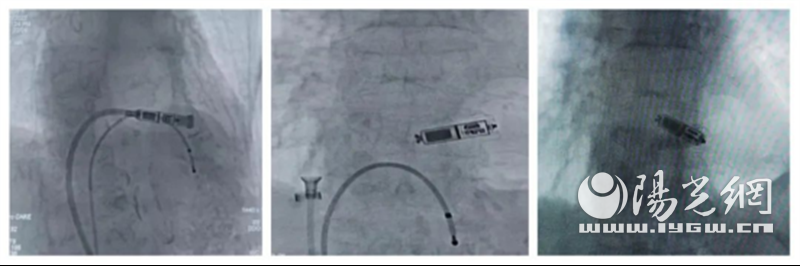

2月16日,心内科李志立主任、张龙副主任为张阿姨进行了无导线起搏器植入术,手术顺利。术后,张阿姨安返病房,目前恢复良好,在科室接受后续治疗。

那么什么是无线心脏起搏器?韩笑医生表示,无线心脏起搏器技术是采用介入技术将起搏器经股静脉入路,植入右室心尖部。

Micra起搏器长度25.9mm,体积1cm³,重量1.75g,直经6.7mm,为全球最小的心脏起搏器。全身3.0T核磁兼容。该技术2018年在国内首次开展,对于科室的技术水平有较高要求。

与传统的起搏器相比,Micra起搏器具有不用开刀,不用植入导线,创伤小、恢复快、住院时间短的优点,是缓慢性心律失常患者治疗的福音。